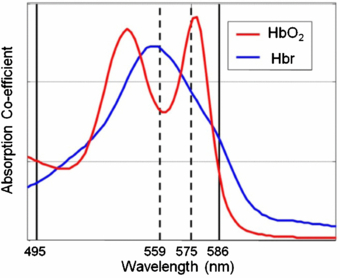

3.3. Photoacoustic tomography